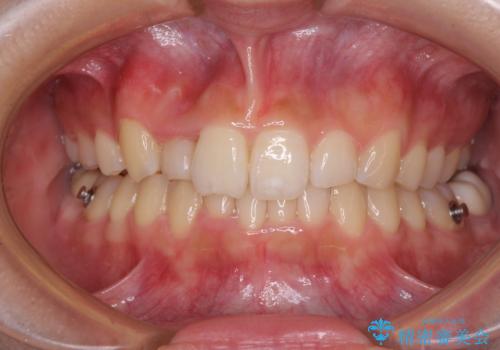

気になる八重歯を改善 補助装置併用のインビザライン治療

- 上顎の重なっている前歯を気にして来院された患者様です。

八重歯改善には抜歯が必要で、八重歯の移動量が多く、更には右側にずれている正中を改善する必要がありました。

インビザライン単体での治療は困難と判断し、補助装置により八重歯移動後にインビザラインを用いることとしました。

インビザラインでは治療期間が延びることが予想されたため、ワイヤー矯正を提案しましたが、セラミッククラウンが多く、壊すあるいは傷が付く可能性があることから、長期間であってもインビザラインを選択されました。